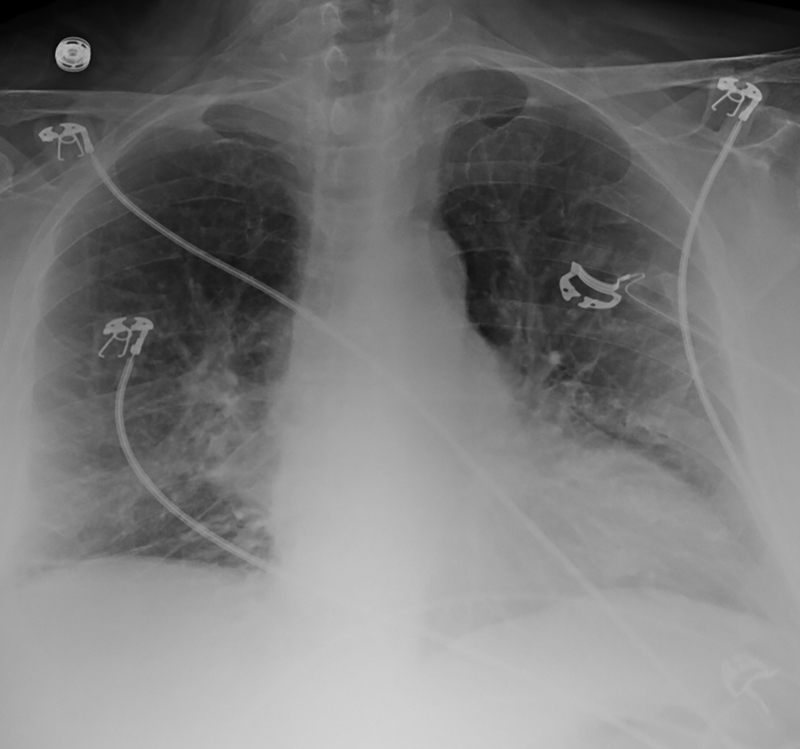

An 83-year-old woman living in rural New Mexico with past medical history significant for Alzheimer’s dementia and Type II diabetes mellitus was hospitalized for four-day history of malaise, anorexia, fever and dyspnea. On initial presentation, the patient was hypoxic on room air with a heart rate of 101 bpm, respirations of 33 bpm, blood pressure of 117/74 mmHg and temperature of 99°F. CXR on admission showed bilateral infiltrates (Figure 1). Computed tomography with angiography was performed and was negative for pulmonary embolism but showed diffuse bilateral ground glass opacities (Figure 2). Diagnostic workup revealed leukocytosis (12.1 K/mcL), platelet count of 115 (K/mcL), hemoglobin of 16.6 (g/dL), and hematocrit of 47.4%. The patient had normal renal function on admission. A transthoracic echocardiogram showed preserved ejection fracture and no acute valvular pathology. Testing was negative for influenza A/B PCR, COVID-19 PCR, viral PCR panel, ANA, Mycoplasma IgM and Streptococcus pneumoniae and Legionella urinary antigens. Due to the location of the patient’s home residence, as well as reports of exposure to mice, serology testing for Hantavirus was sent. The patient was placed on empiric antibiotics for presumed community-acquired pneumonia but deteriorated during her third hospital day, with worsening hypoxia ultimately requiring endotracheal intubation with mechanical ventilation. Initial PaO2/FiO2 ratio was 133 and later deteriorated to 87. A repeat chest X-ray showed worsening diffuse bilateral patchy opacities (Figure 3). Blood, urine and sputum cultures returned negative. The patient developed refractory hypotension despite fluid resuscitation and required increasing amounts of vasopressor support. Lab work reflected worsening hemoconcentration despite intravenous fluid administration. The family ultimately elected for conversion to palliative measures, and the patient passed away with comfort care. Serology testing for Hantavirus later returned positive for IgM and IgG.

Figure 1

Figure 1. Portable chest x-ray reveals bilateral infiltrates.